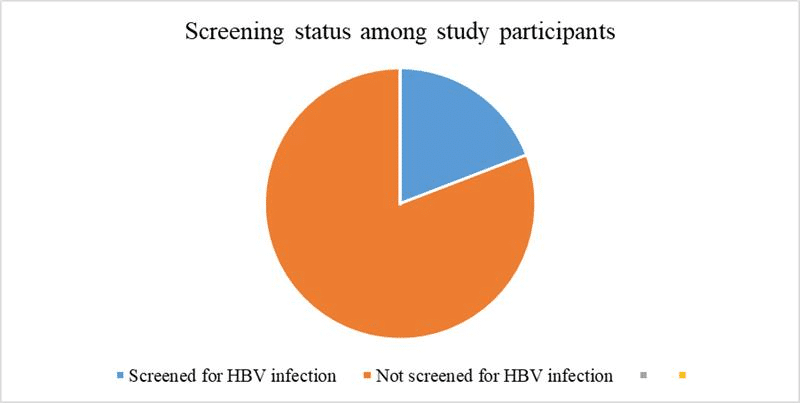

Knowledge, Attitude, and Practice Towards Hepatitis B Vaccine Among Clinical Year Students in University of Gondar College of Medicine and Health Sciences, Northwest, Ethiopia: An Institution-based Cross-sectional Study

Background: Hepatitis B is a viral infection that attacks the liver and can cause both acute and chronic disease. It...Read More